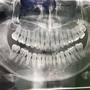

[問卦] 該拔智齒嗎(圖

[ Gossiping ]28 留言, 推噓總分: +8

作者: Superxixai - 發表於 2025/07/26 12:38(4月前)